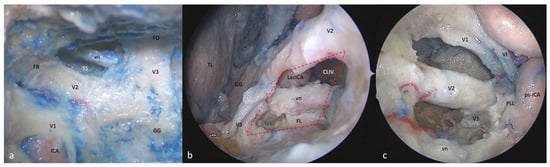

3.6. Anterolateral Triangle

3.6.1. FTOZ Perspective

3.6.2. SETOA Perspective

- (a)

- A wider superior window (“supravidian”) that discloses two corridors in relationship to the lacerum segments of the ICA: a “medial supravidian corridor” leading to the lower clivus, and a “lateral supravidian corridor” leading, after gentle lateralization of the Gasserian ganglion, to the medial aspect of the Meckel’s cave and the terminal portion of the horizontal petrous ICA (pICA).

- (b)

- A narrow inferior window (“infravidian”) that includes the inferior portion of the foramen lacerum distally, and the sphenoid sinus proximally.

3.6.3. EEEA Perspective